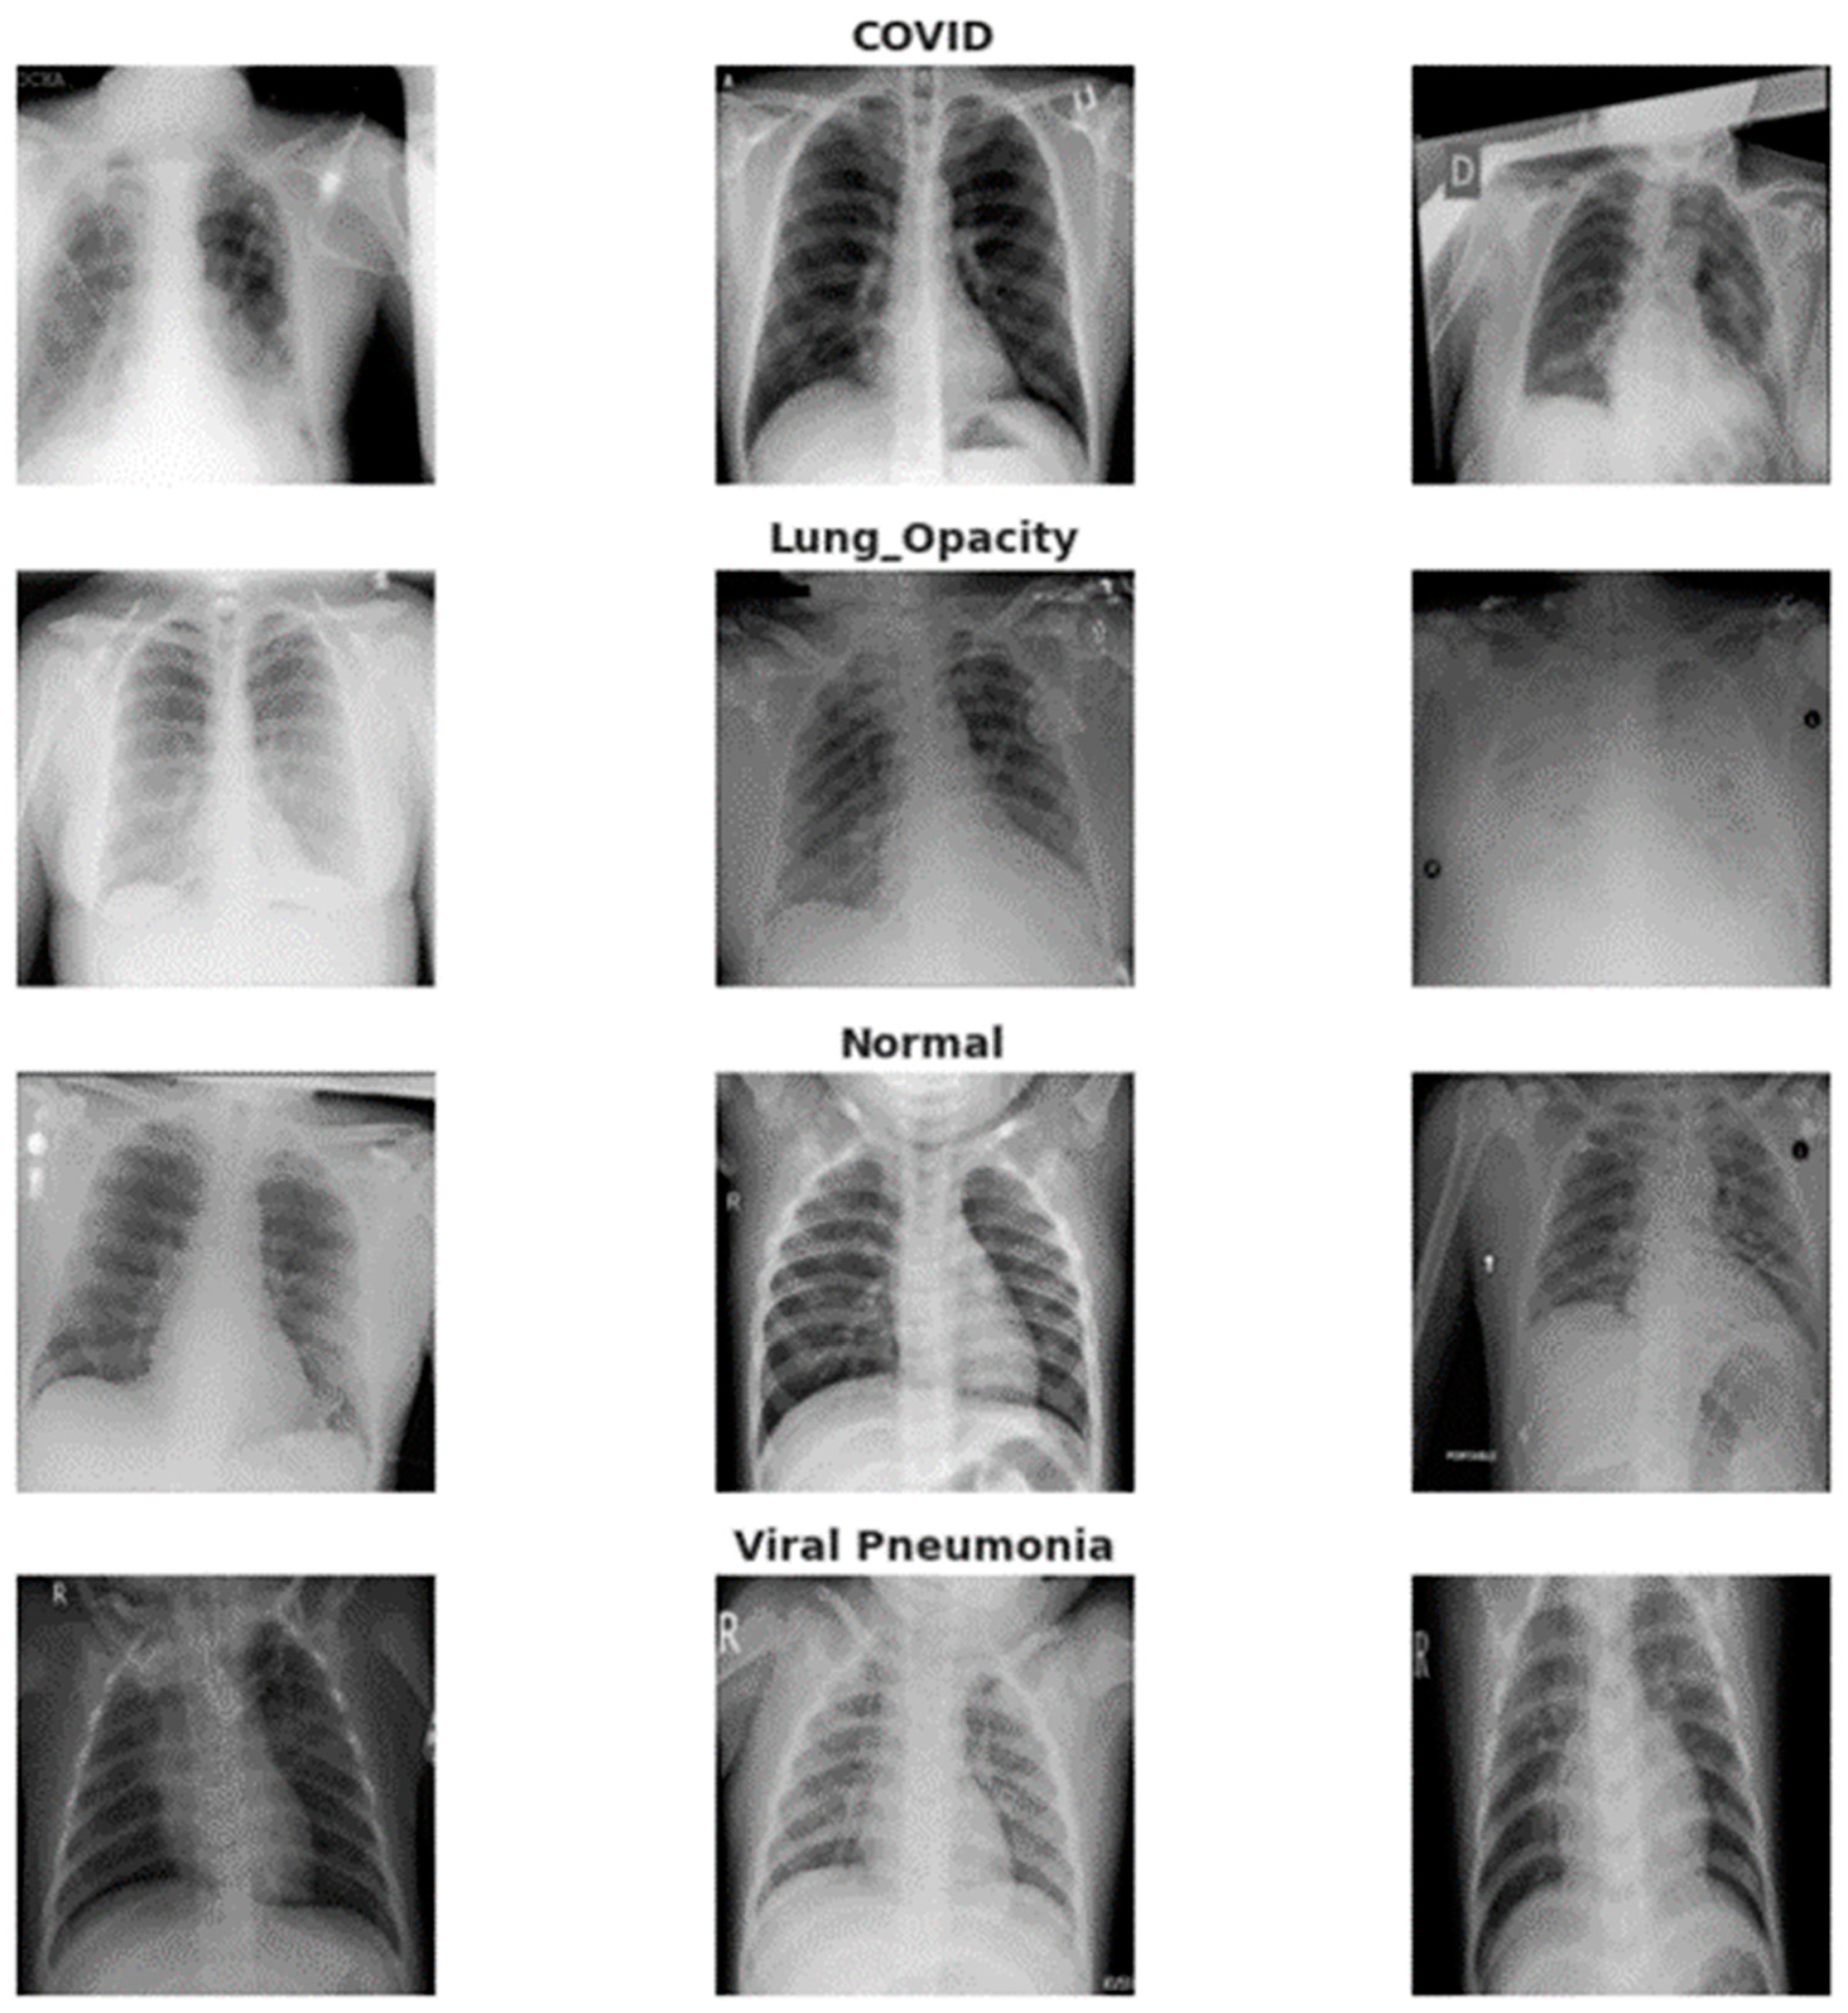

3.1. Data Acquisition

| Category | Images | Data Augmentation |

|---|---|---|

| Normal | 375 | 12,000 |

| Pneumonia | 345 | 12,000 |

| COVID-19 | 375 | 12,000 |

| Lung Opacity | 400 | 12,000 |

| Total | 1495 | 48,000 |